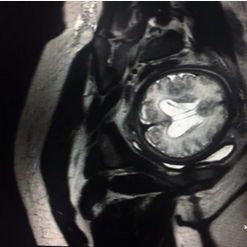

A:当然可以,一般胎儿我们建议孕期3个月以上孕妇检查,彩超在胎儿筛查中最常用,但是如果某些胎儿病变或者发育异常彩超无法明确时,磁共振就成了我们的不二选择;对于心脏的MRI检查技术已经相当成熟,我科有专业团队负责扫描与诊断,而且常常在CT上才能做的冠脉成像,在我们MRI上也可以完成,并且无需注射造影剂。

上图分别为成人、儿童(5岁)冠脉成像;

上图分别为胎儿头颅及胎盘成像